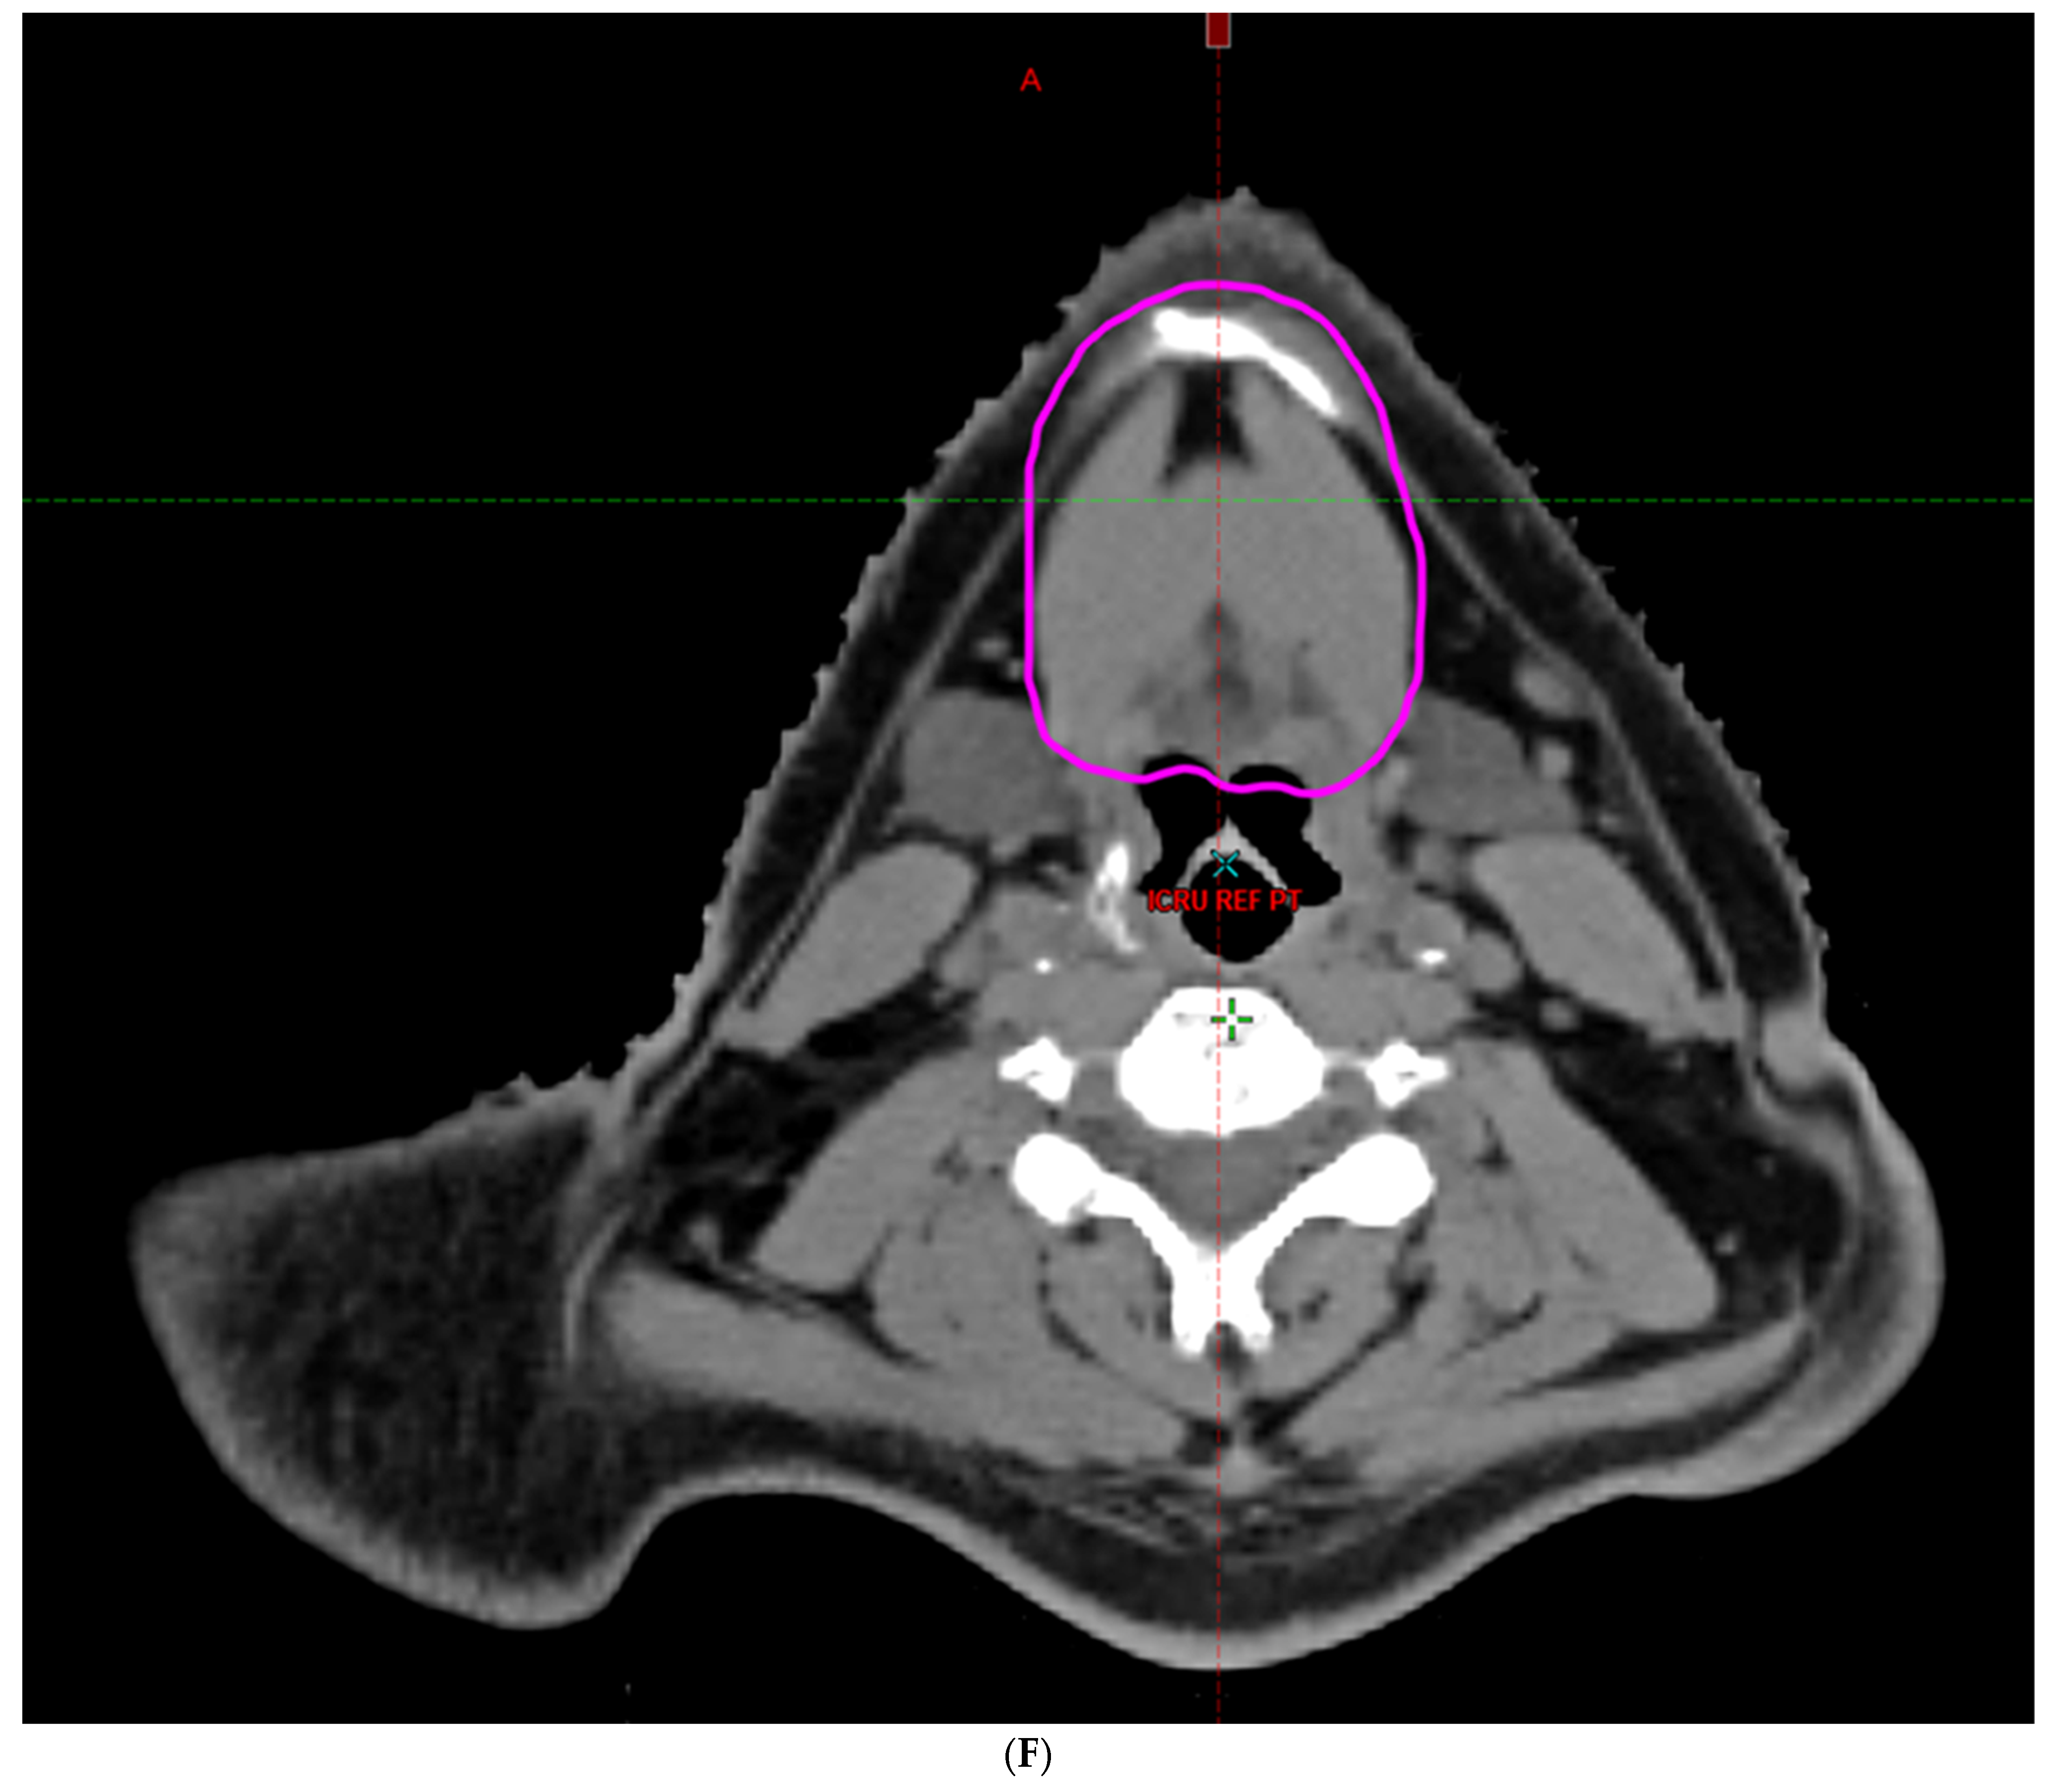

- Hoebers, F.; Yu, E.; Thorstad, W.; O’Sullivan, B.; Dawson, L.A.; Hope, A. A Pragmatic Contouring Guideline for Salivary Gland Structures in Head and Neck Radiation Oncology. The MOIST Target. Am. J. Clin. Oncol. 2013, 36, 70–76. [Google Scholar] [CrossRef]

- Brouwer, C.L.; Steenbakkers, R.J.; Bourhis, J.; Budach, W.; Grau, C.; Grégoire, V.; Van Herk, M.; Lee, A.; Maingon, P.; Nutting, C.; et al. CT-based delineation of organs at risk in the head and neck region: DAHANCA, EORTC, GORTEC, HKNPCSG, NCIC CTG, NCRI, NRG Oncology and TROG consensus guidelines. Radiother. Oncol. 2015, 117, 83–90. [Google Scholar] [CrossRef]

- Li, K.; Yang, L.; Hu, Q.-Y.; Chen, X.-Z.; Chen, M.; Chen, Y. Oral Mucosa Dose Parameters Predicting Grade ≥ 3 Acute Toxicity in Locally Advanced Nasopharyngeal Carcinoma Patients Treated with Concurrent Intensity-Modulated Radiation Therapy and Chemotherapy: An Independent Validation Study Comparing Oral Cavity versus Mucosal Surface Contouring Techniques. Transl. Oncol. 2017, 10, 752–759. [Google Scholar] [CrossRef]

- Sun, Y.; Yu, X.-L.; Luo, W.; Lee, A.W.; Wee, J.T.S.; Lee, N.; Zhou, G.-Q.; Tang, L.-L.; Tao, C.-J.; Guo, R.; et al. Recommendation for a contouring method and atlas of organs at risk in nasopharyngeal carcinoma patients receiving intensity-modulated radiotherapy. Radiother. Oncol. 2014, 110, 390–397. [Google Scholar] [CrossRef]

- Dean, J.A.; Welsh, L.C.; Gulliford, S.L.; Harrington, K.J.; Nutting, C.M. A novel method for delineation of oral mucosa for radiotherapy dose–response studies. Radiother. Oncol. 2015, 115, 63–66. [Google Scholar] [CrossRef]